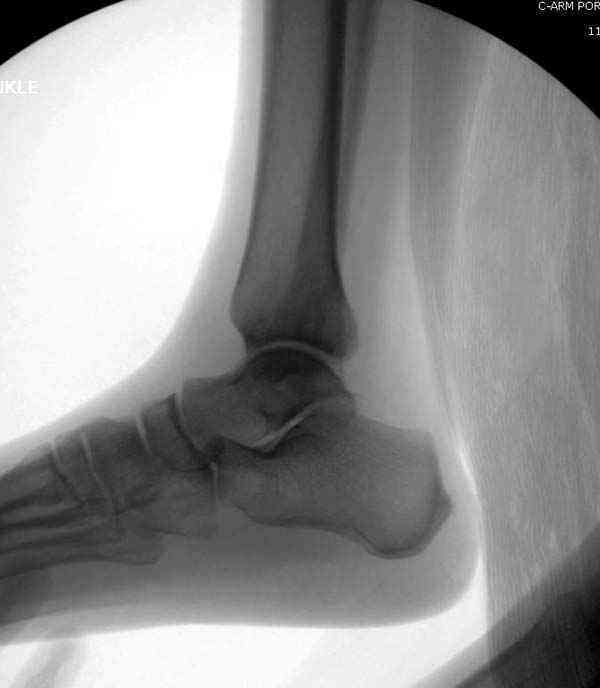

Нет первичных снимков, перелом очень низкий и под большим сомнением диагноз разрыва синдесмоза. Медиальная сторона отрепонирована на "хорошо" и, по-видимому, прорезание проволоки произошло во время операции. Без снимков трудно судить о высоте малоберцовой, а лодыжка находится в варусе. Лагирование получилось, но возле тонких шурупов передне-задний шуруп выглядит немного тяжеловато.

Коллеги правы, что при рутинных переломах достаточным бывает обычные снимки с мортизом. А стрессовые рентгенограммы могут уточнить, есть ли разрыв синдесмоза.

Здесь несколько частных случаев: перелом голеностопа со сравнительными снимками и разрыв синдесмоза, а также медиальная Hook пластина.